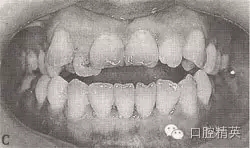

患者,女,29歲。恒牙頜,左上6,左下6,右上6,右下6中性。右上321、右下4321,左上123、左下1234開頜5mm。

右上21、右下4321,左上123、左下123反頜。

右上54、右下65,左上4、左下4對(duì)頜。

前牙反覆蓋6mm

左上3,右下3唇向。右上54、右下65,左上4、右下4舌向。

左下2外翻,右下6、左下6大面積銀汞充填物,上中線右偏0.5mm,

診斷:安氏Ⅰ類,毛氏Ⅳ2+Ⅱ3+Ⅰ1。

圖9-42 開頜病例矯治前的面頜像

圖9-42 開頜病例矯治后的咬合像

治療:減右上4,右下4,左上6后,直絲弓矯治器+MEAW技術(shù)矯治,經(jīng)2年半治療,擁擠、開頜及反頜畸形得以矯治,咬合關(guān)系良好。